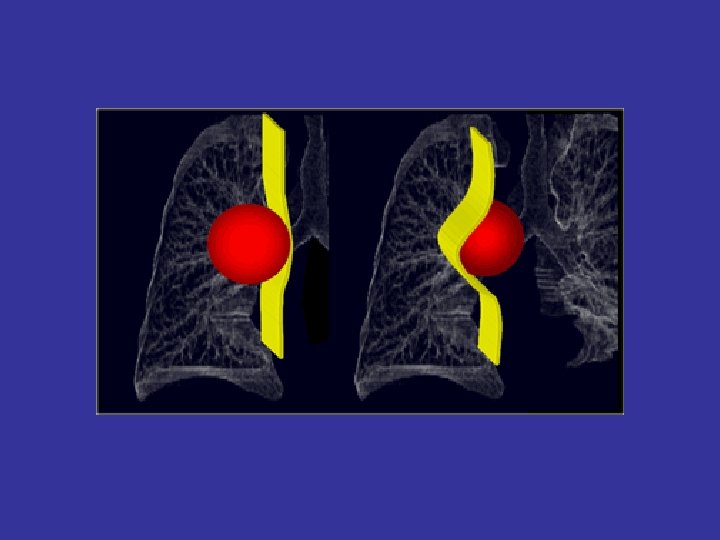

lateral view ? ! can detect otherwise hidden masses

The lateral chest film our best friend • Find abnormalities on the frontal film

The lateral chest film our best friend • Find abnormalities on the frontal film • Confirm abnormalities suspected from frontal film • Don’t be afraid to look at it